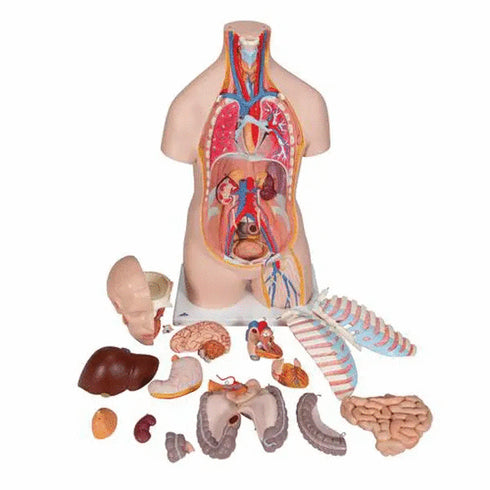

Urmatoarele componente ale acestui tors unisex sunt detasabile:

- cap (3 parti);

- plamani cu stern si coaste (2 parti);

- inima (2 parti);

- stomacul;

- ficatul cu vezica biliara;

- tract intestinal (4 parti);

- jumatatea din fata a rinichiului;

- jumatatea din fata a vezicii urinare.